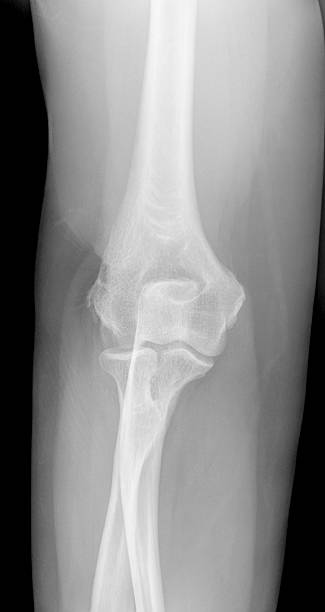

테니스엘보는 테니스엘보라는 이름에 걸맞게 테니스 백핸드 자세에서 팔꿈치 부위에 무리한 힘이 가해지면서 발생하는 팔꿈치 통증으로 정식 진단명은 외측 상과염으로 불립니다. 비단 이 통증은 테니스를 치는 사람에게만 나타나는 것이 아니라 전반적으로 팔을 많이 사용하는 분들에게 나타나며 관리가 잘 되지 않으면 만성질병으로 고착화 될 수 있습니다.

다만, 보존적 치료를 진행하더라도 증상이 나아지지 않는 경우도 있습니다. 이 때는 외과적인 수술적 치료를 진행하는데 수술의 방식은 개방 수술 혹은 변연 절제술, 유리술 등을 통해 진행되며 수술을 하더라도 반드시 재활과 운동 치료를 병행해야만 합니다.